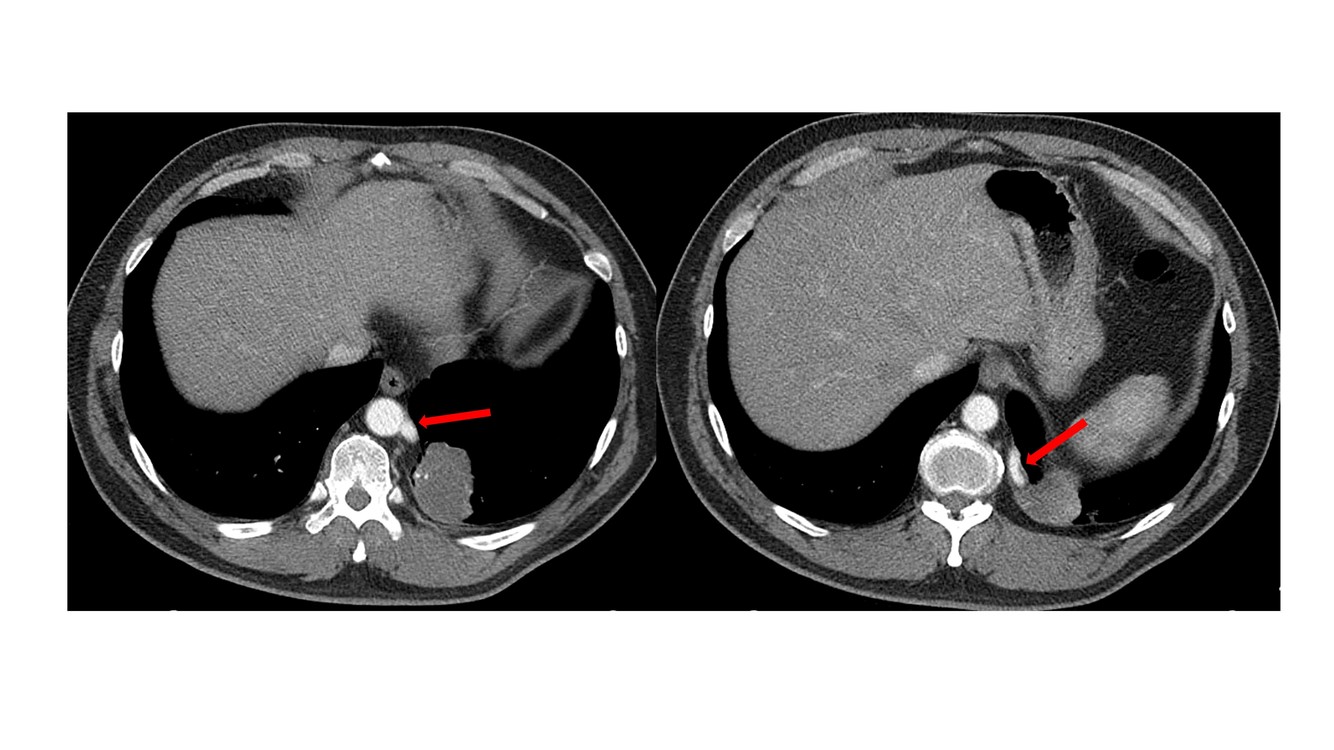

What is this?

A

bronchogenic cyst